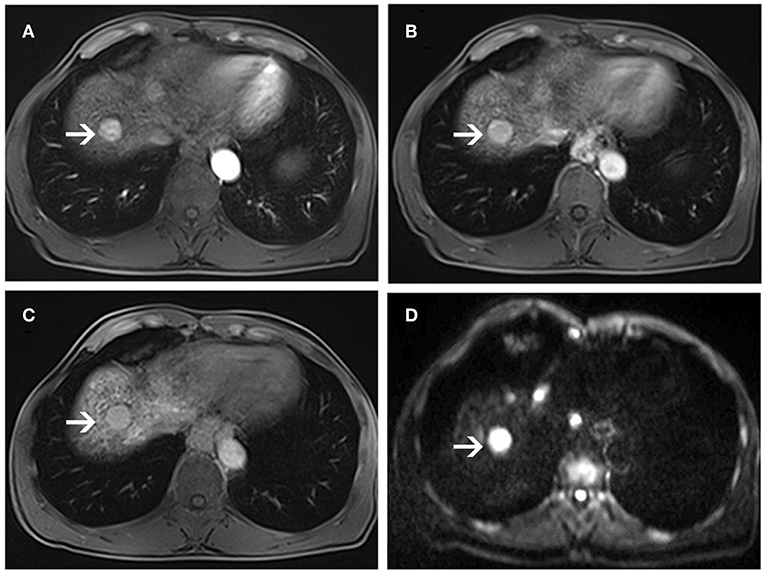

Figure 5. MR images of a 56-year-old man with a pathologically proven high-grade dysplastic nodule (white arrows) and a history of hepatitis B virus infection. Arterial-phase image (A) shows an enhancing nodule in segment VIII of the liver. Equilibrium-phase MR image (B) shows a nodule not demonstrating washout of the contrast material. A hepatobiliary phase image (C) shows nearly isointensity compared to the surrounding liver parenchyma. On diffusion-weighted image (D), the lesion shows hyperintensity compared to the surrounding liver parenchyma.

In DWI set, 41 nodules among the 46 sHCCs showed hyperintensity on DWI (Figure 3), and 5 nodules showed iso/hypointensity on DWI (Figure 4). Of the 27 DNs, 19 nodules (6 HGDNs, 13 LGDNs) showed iso/hypointensity on DWI (Supplementary Figure 3), and 8 nodules (6 HGDNs, 2 LGDNs) showed hyperintensity on DWI (Figure 5). The sensitivity and specificity for identifying sHCCs from DNs in DWI set were 89.1% (41/46) and 70.3% (19/27), respectively.